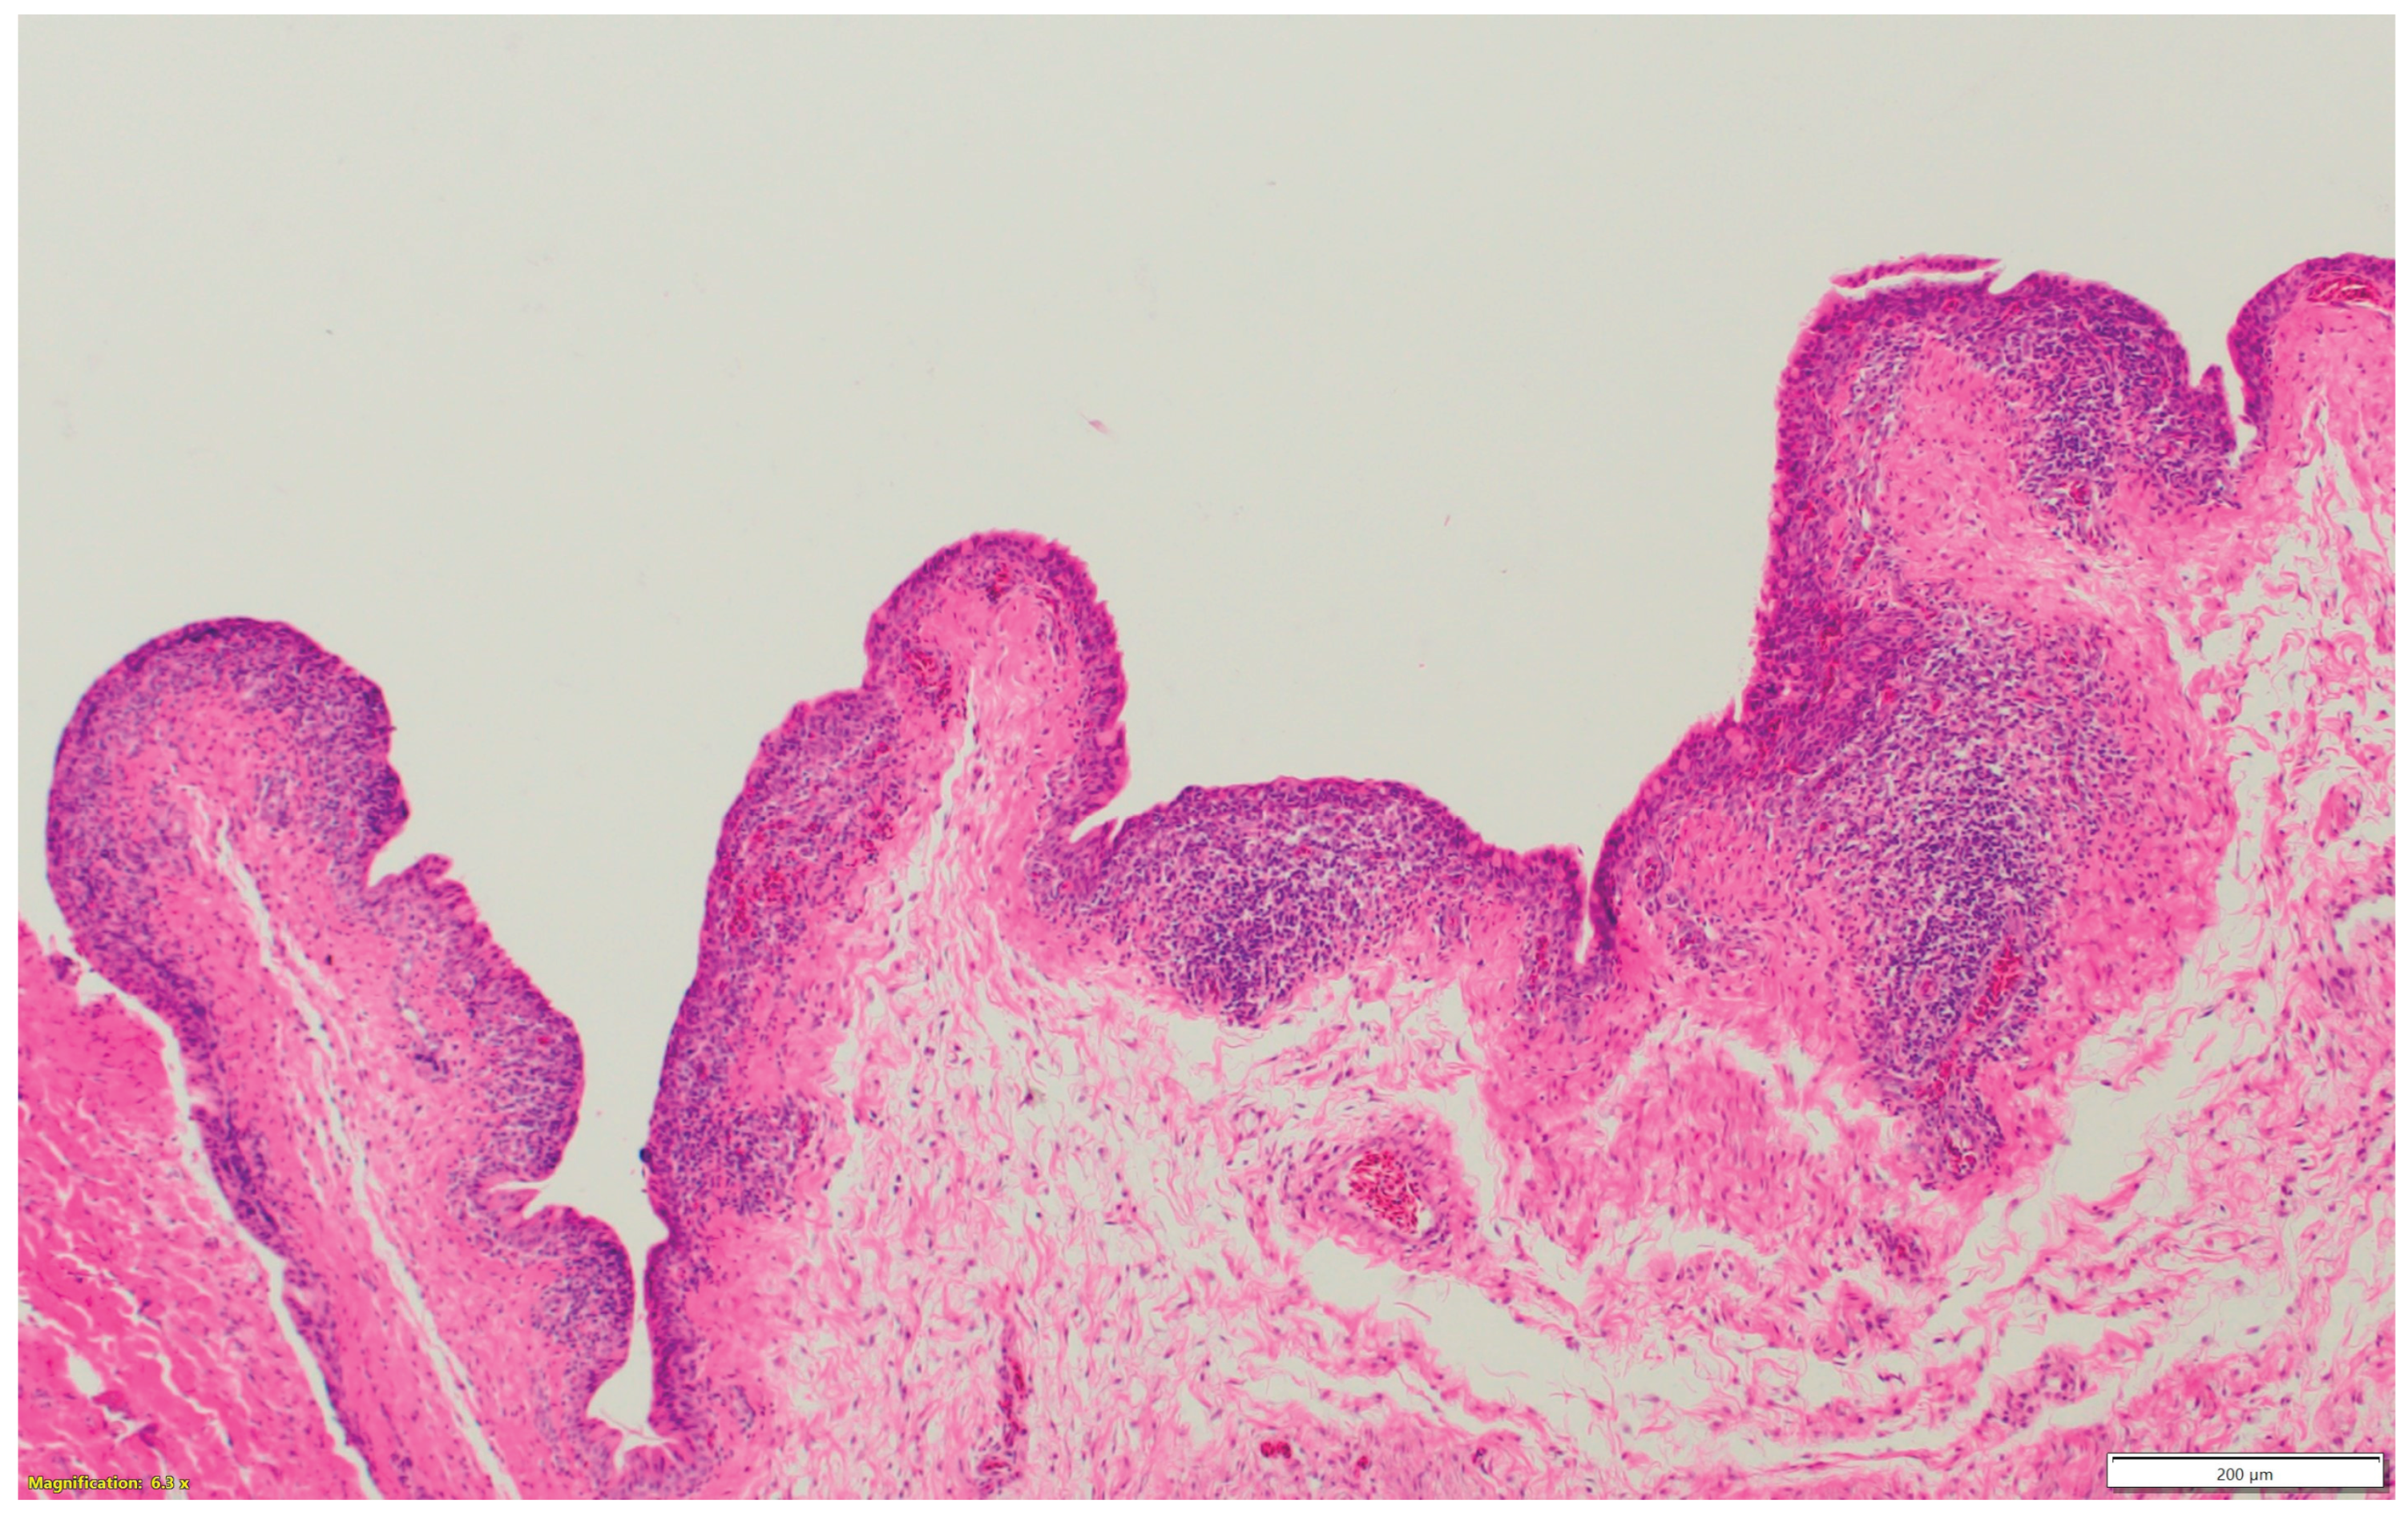

3.1. Turkeys infected with aMPV at 1-day-old (Figure 2a) had a higher total HRI compared with noninfected controls. The gap between the two groups increased significantly as the birds aged. Sinus and eyelid scores were the main contributors to the difference between the control and infected groups. A similar pattern was observed in groups inoculated at 7- and 14-day-old (Figure 2 b-c), but with higher scores. Sinus was the central part of the score difference, followed by the eyelids.

3.2. Chickens infected with aMPV at 7- and 14-day-old (Figure 3a-b): A similar pattern to the turkeys inoculated with AMPV at 7- and 14-day-old. Similarly, sinuses and eyelids created the main difference between the control and infected groups.

3.3. Turkeys inoculated with aMPV at 7 days of age showed higher lesion scores at 10 DPI compared with the non-infected control group. Sinus and eyelids were the main organs scoring points compared with other organs (Figure 4a).

3.4. Turkeys inoculated with low pathogenic avian influenza (LPAI-H4N6) at 7 days of age had also increased histologic lesion scores at 7 DPI compared with the non-infected control group. Sinus, lungs, eyelids, and trachea were orderly contributing to a higher total HRI (Figure 4b).